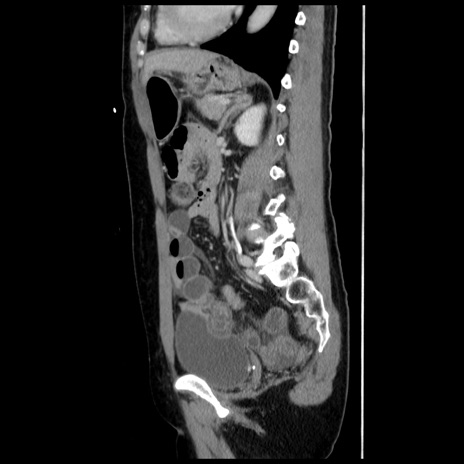

横断像

【症例】 50歳代女性

【主訴】 腹痛

【現病歴】前日生レバーを食べた。今朝に排便あり。 昼前に突然発症の腹痛を生じ、当院救急外来を受診した。

【既往歴】 子宮筋腫にてで子宮全摘後

【身体所見】 意識清明、腹部:平坦、軟、下腹部やや左を中心に圧痛・反跳痛あり、筋性防御あり

【データ】WBC 7800、CRP 0.07